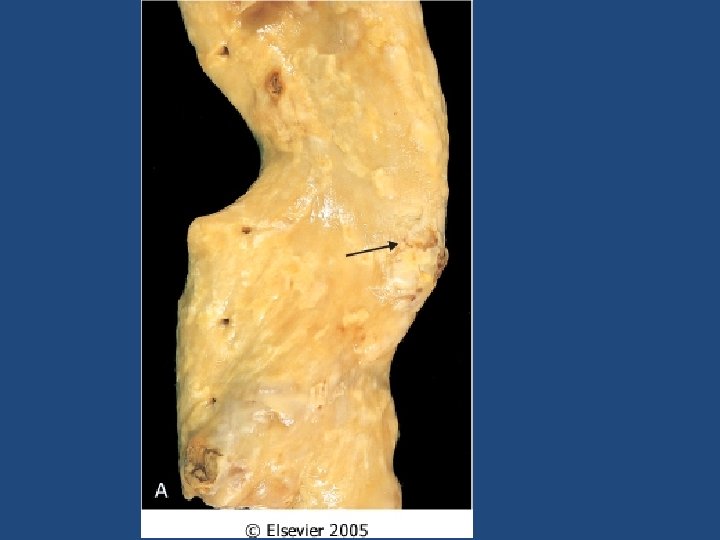

Atherosclerosis • A type of arteriosclerosis • Chronic inflammatory response in the walls of arteries • Slowly progressive • A build-up of fat (cholesterol) within the artery wall • Characterized by intimal lesions called: atheromas, atheromatous or fibrofatty plaques

Atherosclerosis Common sites • • • Abdominal aorta Coronaries Popliteal artery The internal carotid arteries The vessels of the circle of Willis

Morphological changes that are seen on macro and microscopic levels in atherosclerosis • • • Calcification Hemorrhage Fissure Ulcer Thrombosis Neovascularization Medial thinning Cholesterol microemboli Aneurysmal dilatation